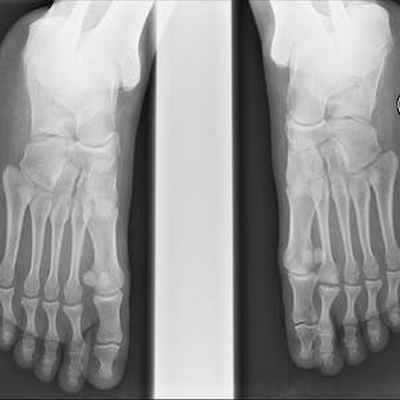

Боль в переднем отделе стопы правой ноги у пациентки 19 лет, в области головки 2-ой плюсневой кости.

Головка 2-ой плюсневой кости выглядит сплюснутой и расширенной с правой стороны в связи с болезнью Фрейберга.

Радиодиагностическое исследование показывает линию перелома, более или менее заметную, расширение суставной щели. Головка сплюснутая и расширена в развитой стадии некроза.

Рентген болезни Фрейберга:

- На картинке выше мы видим остеонекроз (отмирание костной ткани) второй плюсневой кости. Характерный признак болезни Фрейберга.

Диагностика

Диагноз болезни Фрейберга - Келера II может быть подтвержден после клинического обследования с помощью рентгенограмм. На рентгенограммах ног могут наблюдаться незначительные изменения в начале проявления заболевания, характеризующиеся расширением суставного пространства. Расширение может наблюдаться в течение 3-6 недель после появления симптомов. По мере прогрессирования заболевания происходит увеличение плотности кости в субхондральной области и уплощение плюсневой головки.